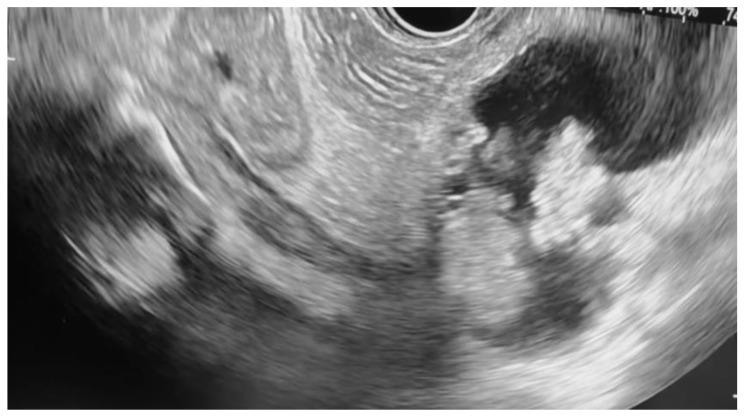

Pancreatic neoplasms, including adenocarcinoma, pancreatic neuroendocrine tumors (pNETs), intraductal papillary mucinous neoplasms (IPMNs), and high-grade cystic lesions, often require surgical resection as a form of curative treatment. However, comorbidities and high-risk features may preclude surgery. Endoscopic ultrasound-guided radiofrequency ablation (EUS-RFA) has emerged as a minimally invasive alternative with proven cytoreductive efficacy in solid tumors. This case series evaluates the safety and efficacy of EUS-RFA in patients with various unresectable, non-metastatic pancreatic neoplasms. A retrospective review was conducted on eight patients who underwent EUS-RFA at our institutions between July 2021 and February 2025. All patients were deemed unsuitable surgical candidates due to comorbidities such as advanced age, cardiovascular disease, renal insufficiency, and COPD or due to patient resistance to surgical intervention. EUS-RFA was performed using a 19-gauge RFA needle (Taewoong Corporation). Follow-up imaging was conducted 3 to 6 months after the completion of RFA treatment. All eight patients demonstrated a good to excellent response in terms of tumor size reduction. The most notable response was observed in a patient with pNET, resulting in complete resolution from 15.6 × 12.0 mm to 0.0 × 0.0 mm after two RFA treatments. Other neoplasms, including pancreatic adenocarcinoma and intraductal papillary mucinous neoplasms (IPMNs), also demonstrated significant reductions. Mild post-procedure complications, including pancreatitis and abdominal pain, were noted in three cases. EUS-RFA is a promising alternative for managing unresectable pancreatic neoplasms in high-risk patients. Our findings support its use across various tumor types with favorable outcomes and minimal complications, reinforcing its role in expanding therapeutic options beyond surgery.

胰腺肿瘤,包括腺癌、胰腺神经内分泌肿瘤(pNETs)、导管内乳头状黏液性肿瘤(IPMNs)和高级别囊性病变,通常需要手术切除作为一种根治性治疗方式。然而,合并症和高风险特征可能使手术无法进行。内镜超声引导下射频消融术(EUS-RFA)已成为一种微创替代方法,在实体肿瘤中具有已被证实的减瘤疗效。本病例系列评估了EUS-RFA在各种无法切除的非转移性胰腺肿瘤患者中的安全性和有效性。对2021年7月至2025年2月期间在我们机构接受EUS-RFA治疗的8例患者进行了回顾性研究。所有患者均因高龄、心血管疾病、肾功能不全和慢性阻塞性肺疾病等合并症或患者对手术干预的抗拒而被认为不适合手术。使用19号射频消融针(太永公司)进行EUS-RFA。在射频消融治疗完成后3至6个月进行随访成像。所有8例患者在肿瘤缩小方面均表现出良好至优异的反应。在1例pNET患者中观察到最显著的反应,经过两次射频消融治疗后,肿瘤从15.6×12.0毫米完全消退至0.0×0.0毫米。其他肿瘤,包括胰腺腺癌和导管内乳头状黏液性肿瘤(IPMNs),也表现出显著缩小。3例患者出现了轻度术后并发症,包括胰腺炎和腹痛。EUS-RFA是管理高危患者无法切除的胰腺肿瘤的一种有前景的替代方法。我们的研究结果支持其在各种肿瘤类型中的应用,具有良好的疗效和最小的并发症,强化了其在扩展手术以外治疗选择方面的作用。